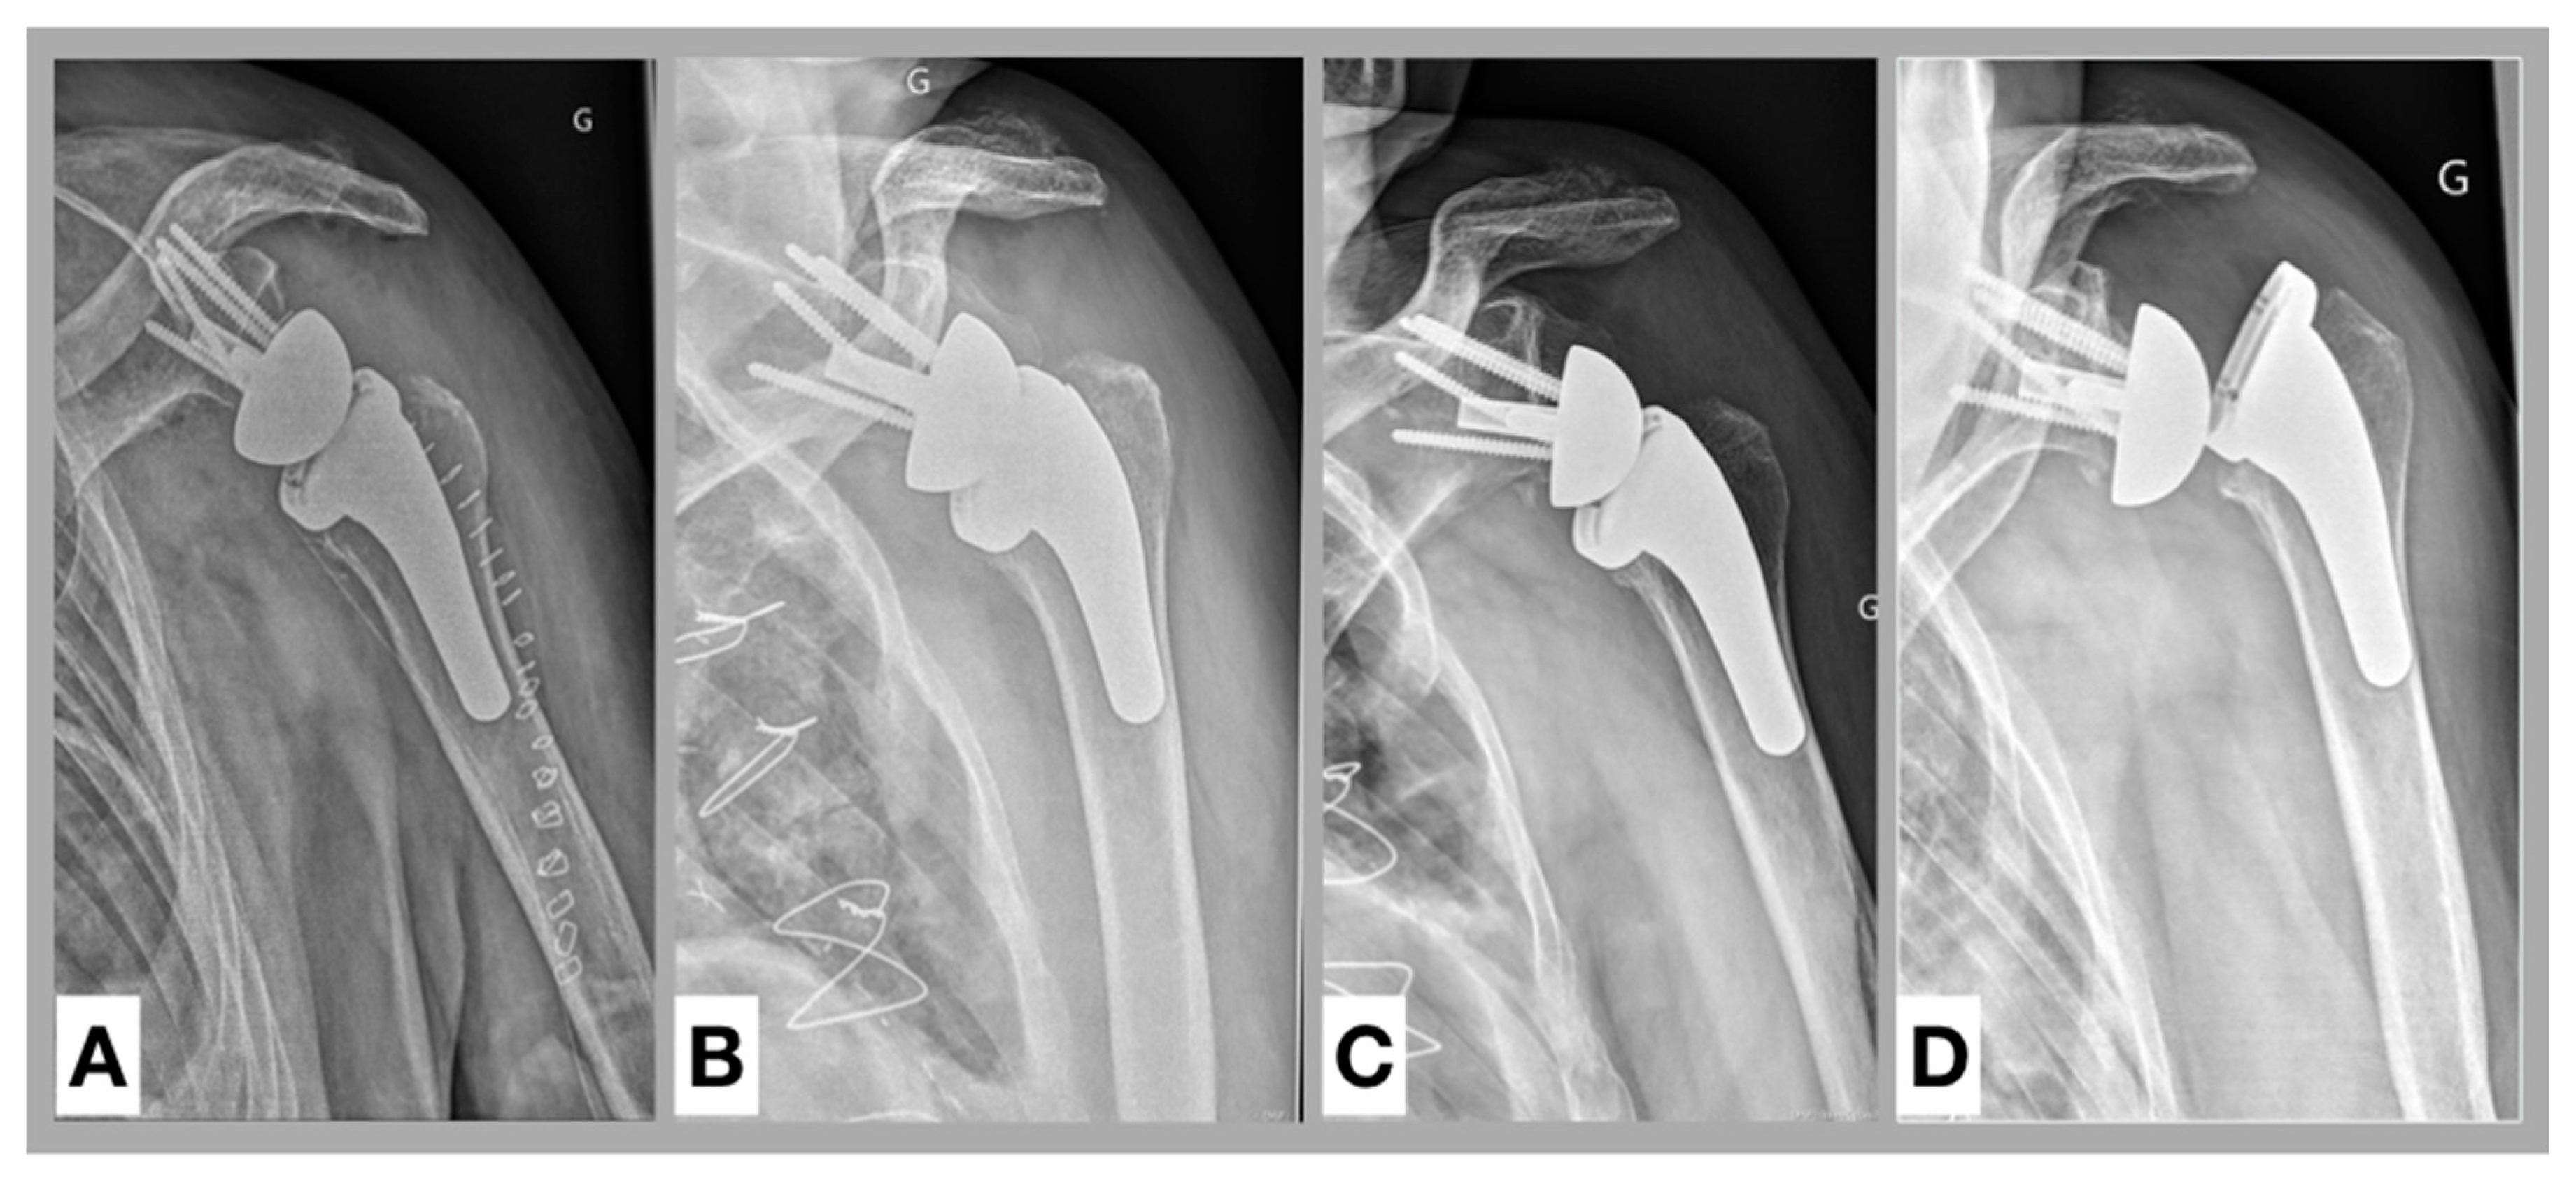

In the past, subsidence was described as a phenomenon rather related to glenoid loosening [43]. Boileau et al. [44] claimed that fixation of a RSA may be more problematic on the humeral side than on the glenoid side, and some of the potential reasons for these complications such as humeral subsidence or loosening may be related to the fact that the humeral stem is round and offers very little resistance to rotational torque. A possible complication following subsidence is a dissociation between the tray and the stem and was found during our patient recruitment (Figure 4). Although this specific case had to be excluded due to suboptimal rotation in the anteroposterior X-ray view, surgeons should be alert to this potential complication.

Figure 4. Complication following subsidence. Anteroposterior radiographs of a left shoulder. (A). Postoperative, (B). 3 months follow-up, (C). 6 months follow-up, (D). 9 months follow-up: Due to subsidence a dissociation between the tray and the stem (Morse taper) occurred.